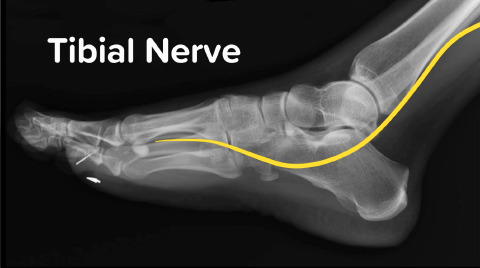

Posterior Tibial Nerve Block

Dr. Jacob Avila walks us through how to anesthetize the distribution of the posterior tibial nerve.